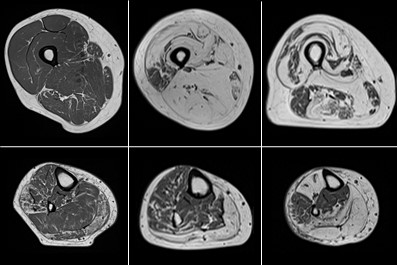

Computational anatomy aims to develop computer processing methods to enrich diagnosis by extracting objective and clinically useful information from medical images. The deployment of such methods remains limited for the exploration of soft tissue organs, especially for the study of pelvic floor disorders and neuromuscular diseases via magnetic resonance imaging. In these domains, the segmentation step is essential to allow the characterization of physiological alterations occurring within the organs of interest. The high phenotypic variability in these pathologies has so far limited the development of robust automatic segmentation methods, limiting clinical research on large populations. To overcome this challenge, the main contribution of my thesis was the development of a supervised segmentation approach based on diffeomorphic image registration propagation methods.

Characterization of physiological alterations in skeletal muscle by quantitative MRI

The development of segmentation methods for muscle soft tissues has allowed the 3D exploration of MRI images on large populations of patients with neuromuscular diseases. The transposition of our methodology into user-friendly tools has enabled us to overcome the barrier of clinical use. Therefore, in collaboration with clinicians from the neurology department of the CHU de la Timone in Marseille, several studies have been conducted on the characterization of physiological alterations occurring at the level of individual muscles in various pathologies and during physical exercises. These studies have notably confirmed the potential of quantitative MRI scores as biomarkers of neuromuscular pathologies.